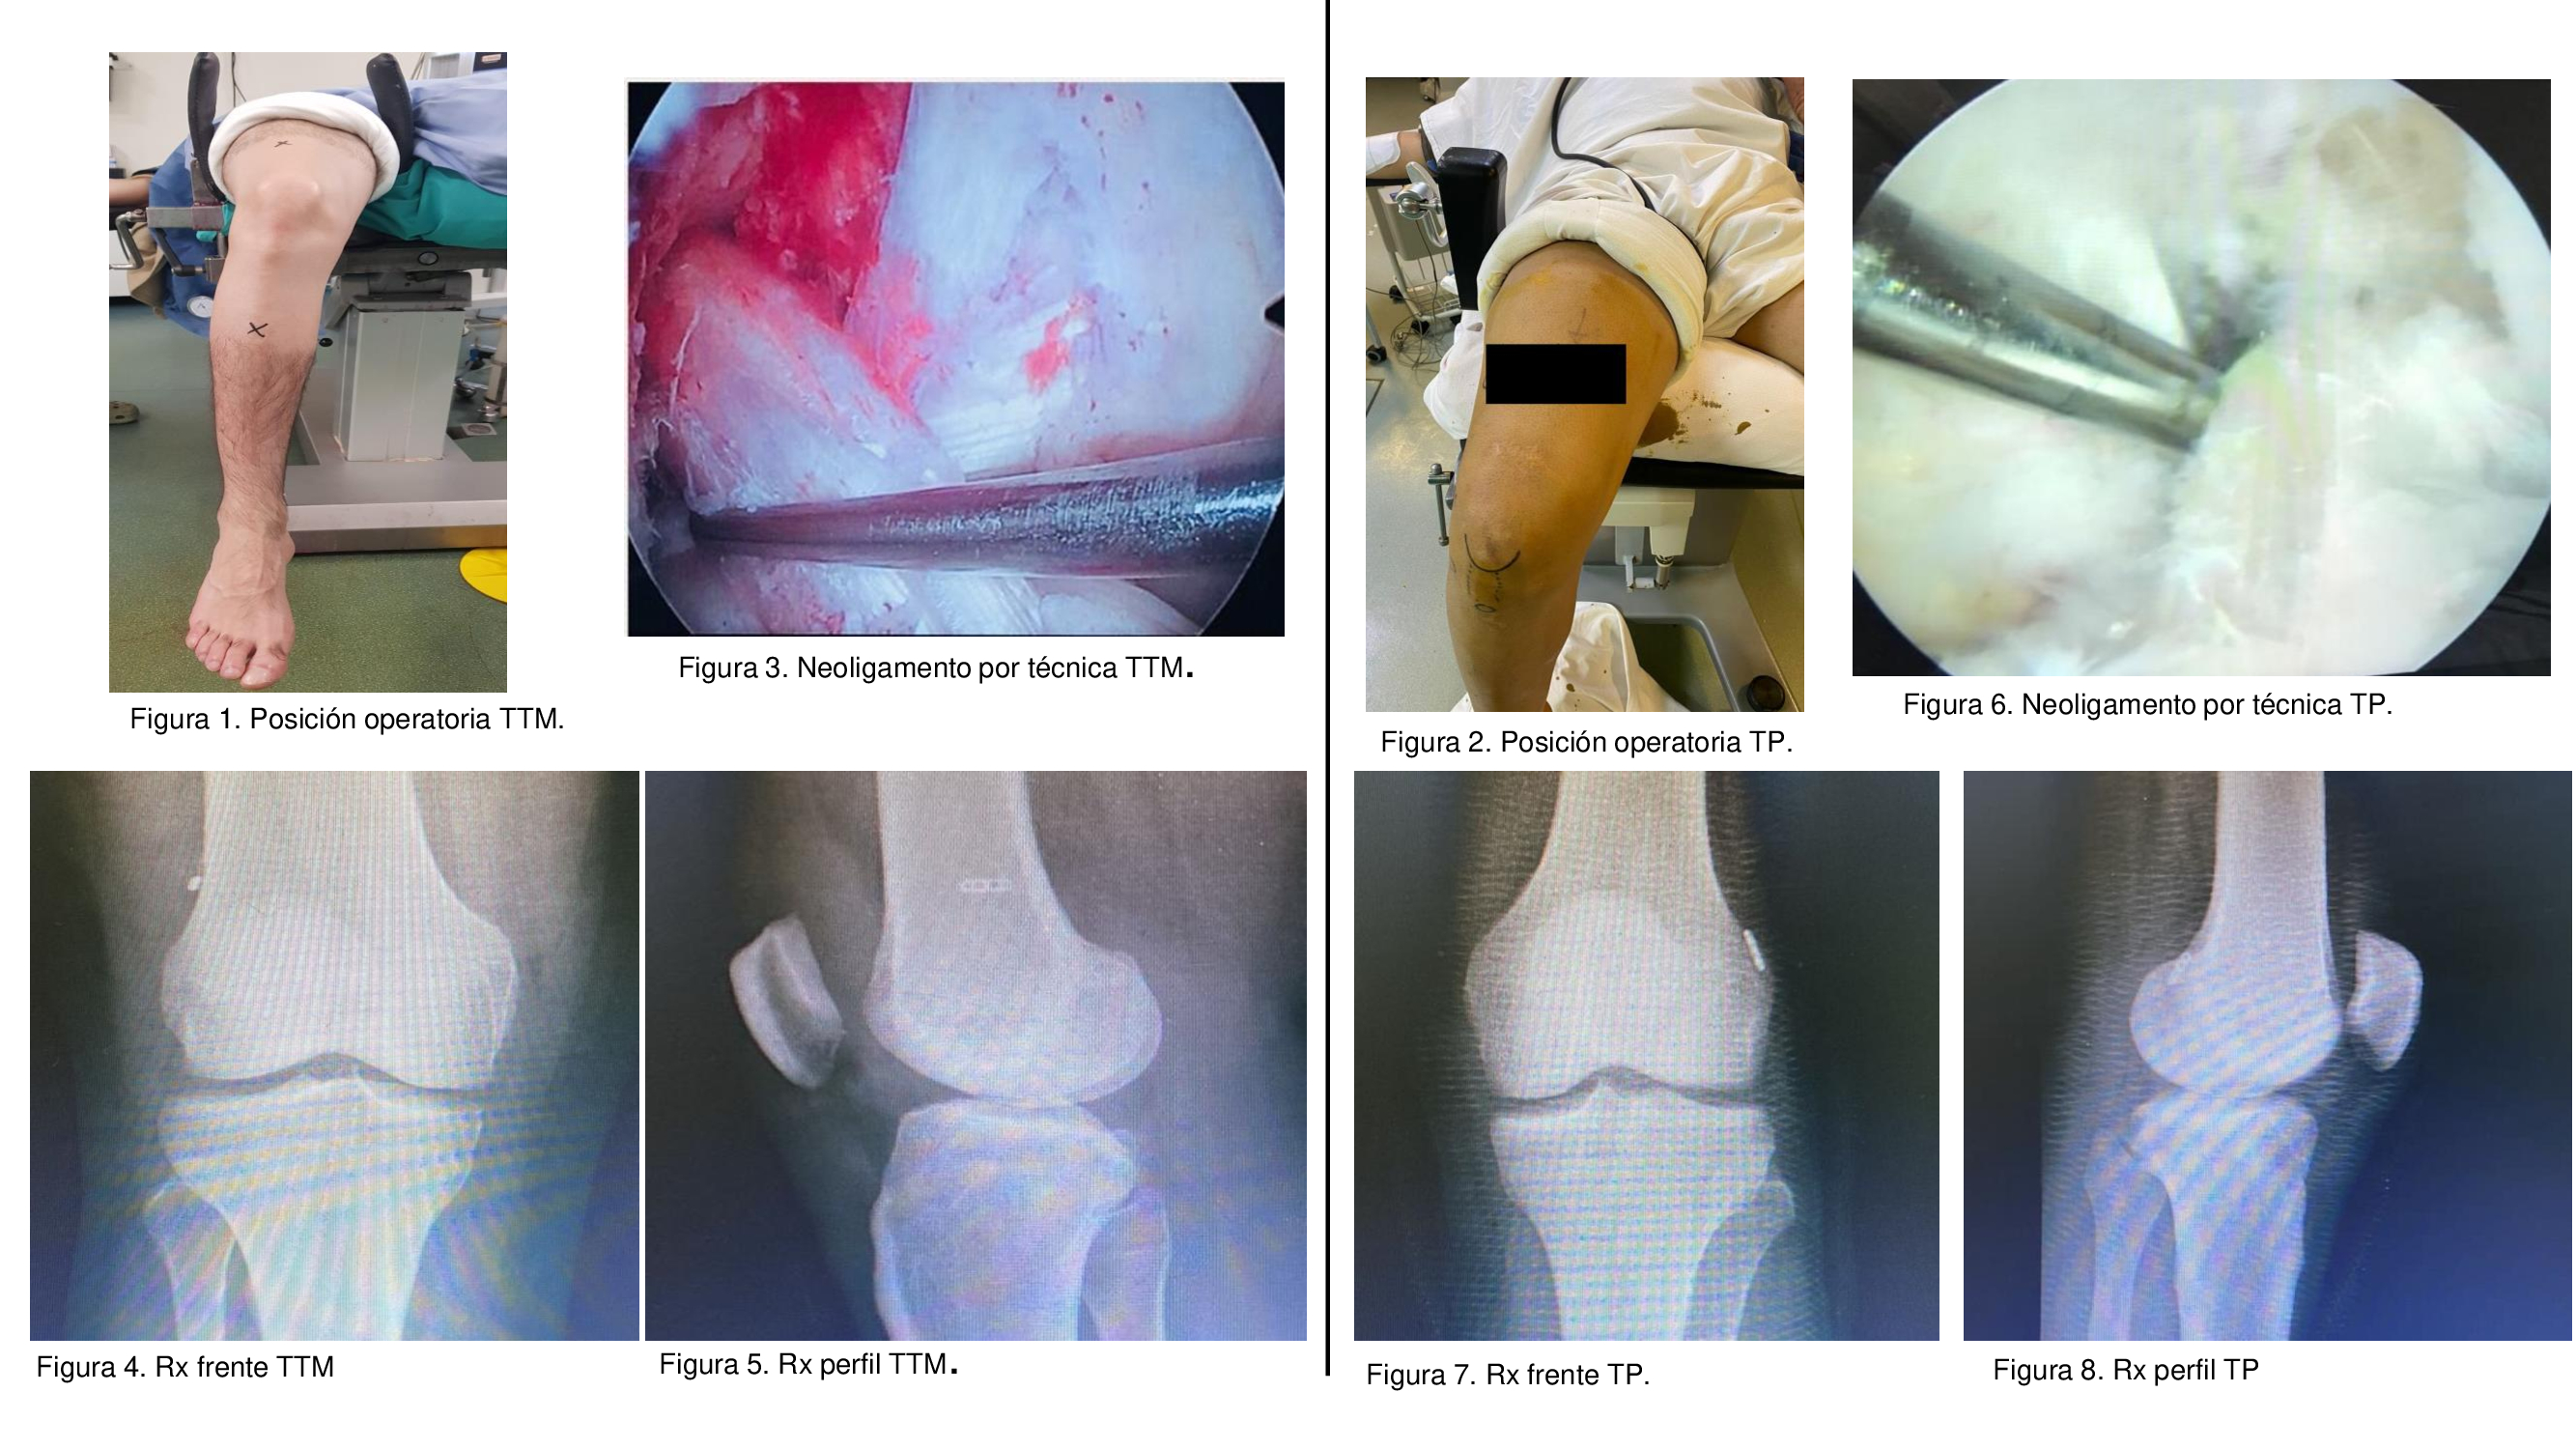

03_“Consideraciones técnicas pre e intraoperatorias entre la reconstrucción transtibial modificada y transportal en lesiones del ligamento cruzado anterior. Resultados clínicos y funcionales”

Dres. Lucas Martín Fernández - Carlos Bianchi - Gabriel Martínez Lotti - Fabián Bianchi - Joaquín Chale. (Rosario, Santa Fe)